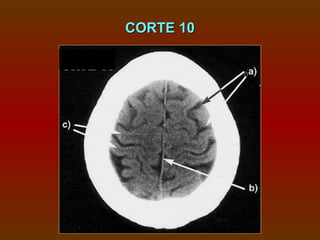

CORTE 10

a) Sulcos

b) Foice cerebral

c) Circunvoluções